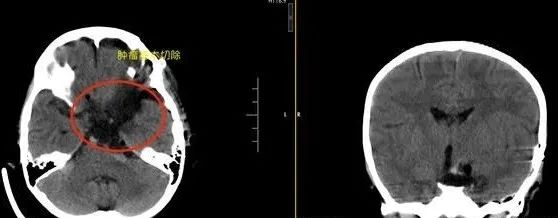

▲术前影像检查

我院头颅CT检查结果出来后,林女士吓坏了。小秋撞到的地方并无大碍,却查出她颅内鞍区三脑室存在占位性病变。杨宝应告诉林女士,初步怀疑是肿瘤。

结合影像资料及临床病症,杨宝应认为患儿颅内病变是颅咽管瘤,由于肿瘤已有出血迹象,建议尽快手术。